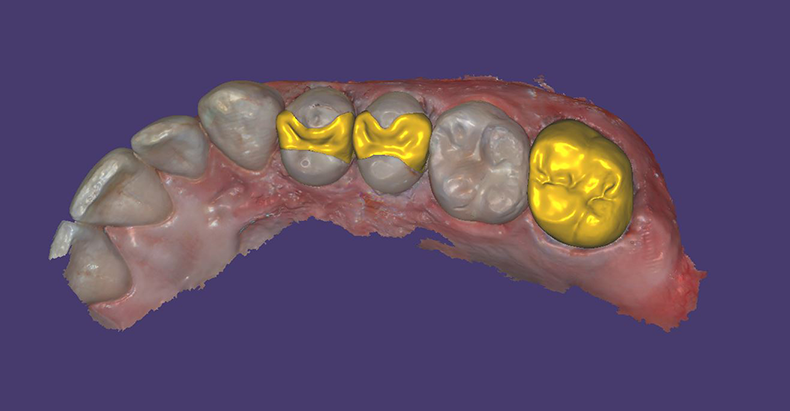

Visual examination revealed decay on the mesial marginal ridge and distal marginal ridge of tooth #13 as well as extensive buccal and occlusal decay on tooth #15 (Figs. 1-2). Bitewing radiographs and intraoral photographs were taken, which confirmed the above diagnosis and also exposed additional decay on the distal of tooth #12 (Figs. 3-4).

Figs. 1 and 2

The tooth was prepped and the CS 3600 intraoral scanner was used to scan the preparation sites and surrounding dentition to create the digital model (Fig. 5). This digital model would be later used to plan the preparations in computer-aided design (CAD) software (Figs. 6-7).